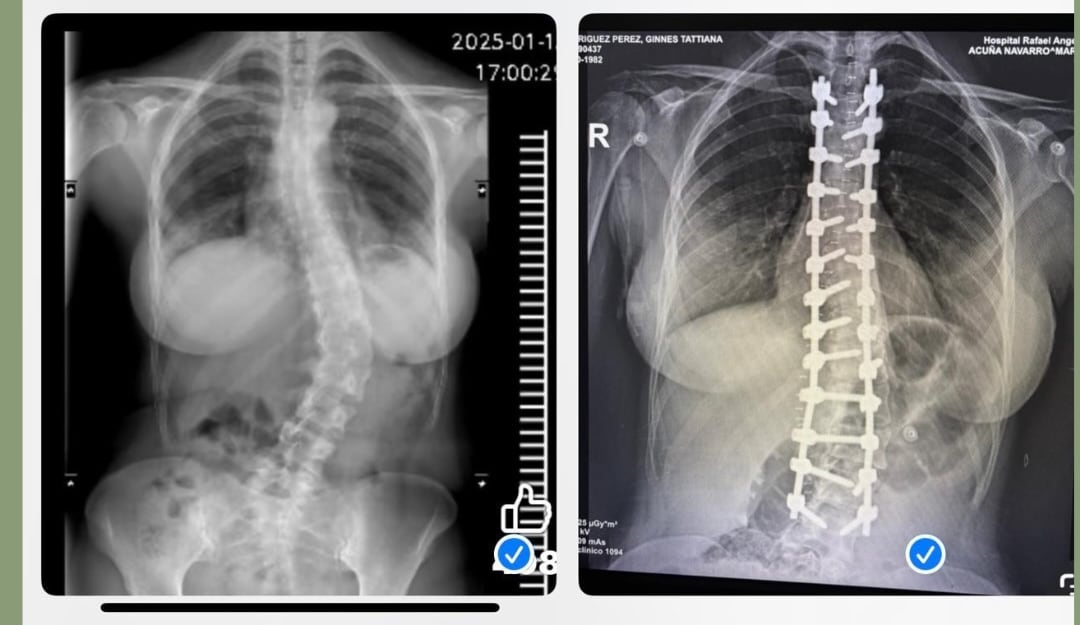

Ginnés Rodríguez fue operada el 17 de marzo de su columna, tras sufrir de escoliosis desde sus 15 años, y mostró el antes y después de su espalda tras la cirugía.

Lo más sorprendente es ver la placa de su columna, ver cómo era antes y cómo luce ahora de recta tras la colocación de los tornillos. Además, se evidencia cómo ahora la figura de su espalda luce más esbelta y ya no se le ve un lado de la cadera más alta que la otra.

Dichas imágenes las compartió en la página de la asociación Alivia tu escoliosis Costa Rica, de la cual la presentadora de Repretel es miembro tras ser diagnosticada con dicha enfermedad.

De hecho, ellos destacaron su proceso con un mensaje cargado de significado y lo titularon: “El antes y el después de otra guerrera de titanio”.